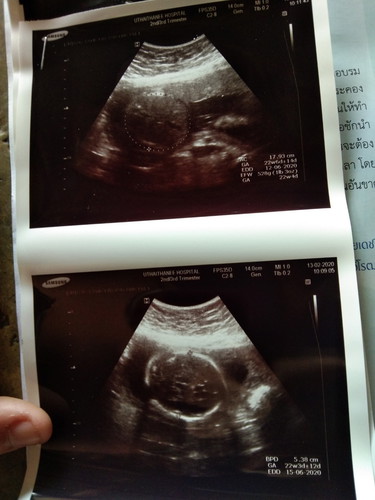

22w4d แข็งแรง สมบูรณ์ทุกอย่าง ปากไม่แหว่ง กะโหลกกลมเต้ม ได้ยินหมอบอกแบบนี้พ่อกับแม่ก้ดีใจแล้ว หนุ่มน้อย??